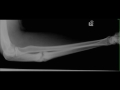

Nonunion of Ulna Fracture on X-ray

Old trauma. X-ray of the left forearm demonstrates an old fracture of the proximal ulna with remodeling. The fracture line is still visible compatible with nonunion. The patient had continued pain one year after fracture.